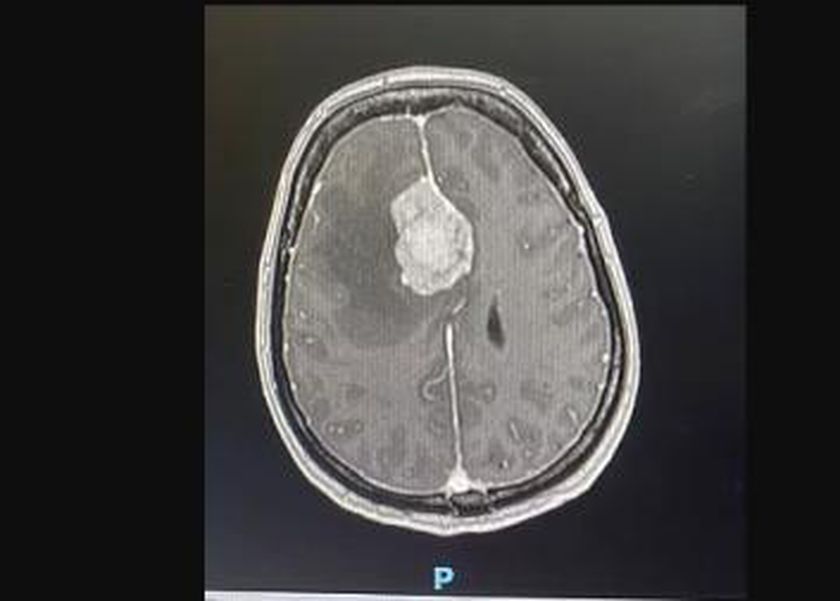

أعراض بسيطة لسيدة في عامها الـ60، كشفت عن إصابة بالورم السحائي، بدأت بنوبات الدوار ومشاكل في التوازن، وإرهاق شديد، شُخّصت في البداية التهاب التيه، وهو مرض يصيب الأذن الداخلية ويؤثر على السمع والتوازن، وعادةً ما يتحسن دون علاج خلال أيام أو أسابيع مع المضادات الحيوية، لكنها لم تتحسن، بل بدأت حالتها تزداد سوءًا.

وقالت صحيفة «ديلي ميل» البريطانية، إنه في مارس 2023، كشفت الفحوصات عن السبب الحقيقي للأعراض، وهو إصابة السيدة وهي سباحة سابقة، بورم سحائي (مينينجيومًا) – وهو ورم ينمو في الأغشية المحيطة بالدماغ.

ما الورم السحائي وكيف يُعالج؟

الورم السحائي يبدأ في طبقة الأنسجة المحيطة بالدماغ والحبل الشوكي، وتُعرف بـالسحايا، وعادةً ما ينمو الورم السحائي ببطء، ولهذا قد لا تكون الأعراض واضحة في البداية، لكن مع نموه، يمكن أن يضغط على المناطق القريبة من الدماغ، ما يؤدي إلى أعراض ذكرتها منظمة «الصحة العالمية»، وموقع «webmd» الطبي، كالتالي: